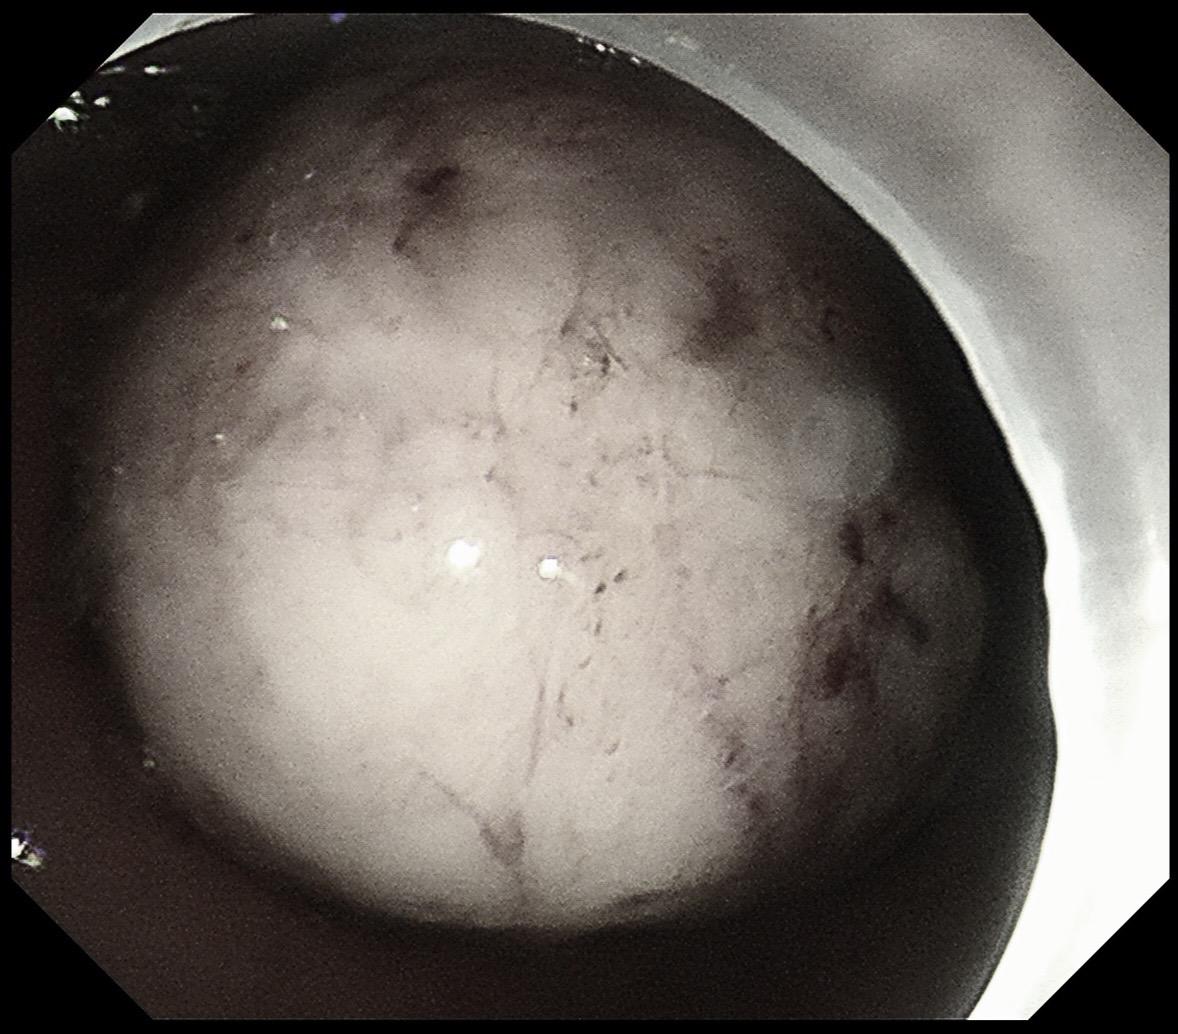

你性命相托,我必全力以赴。感谢信任!86岁,反复消化道出血1年多,血色素最低掉到6克。外科手术有可能保不住贲门,创伤大,家属拒绝。在外科老师备台、麻醉科的给力配合下,历时2个小时5厘米的瘤子完整切除并缝合。这种手术对患者是微创,对医生是巨创!